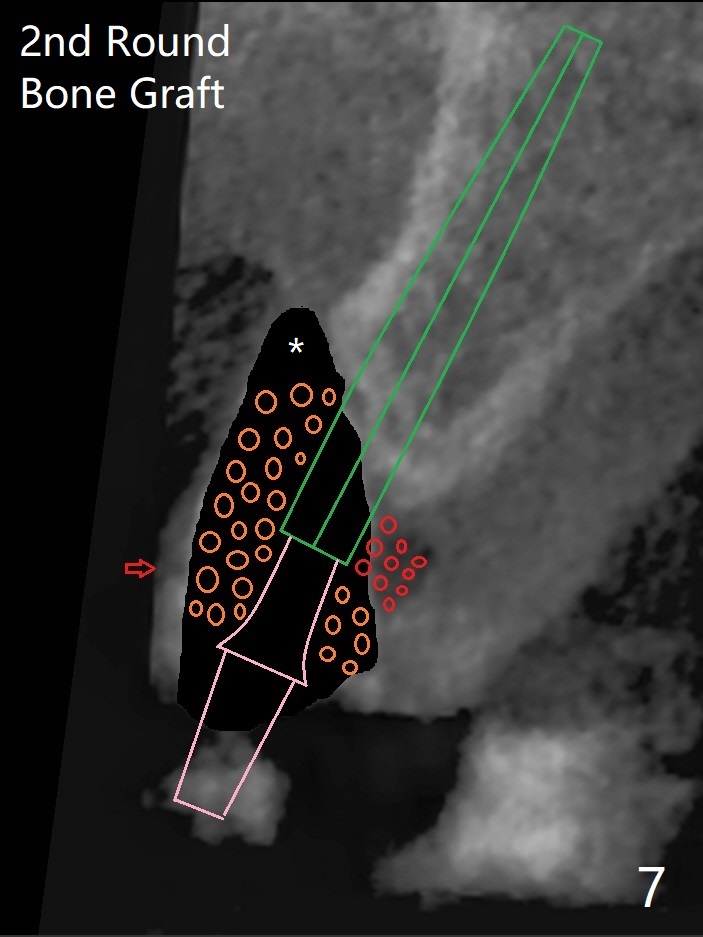

左上尖牙拔除前发现远中腭侧瘘道,拔除后发现相对牙槽嵴骨缺损(图一(术前CT):*),其实患牙根尖在颊侧骨板颊侧(图二:>),拔除后,根尖骨板缺损(图三:>),由于后者离颊侧牙槽嵴(图四:红箭头)远,骨粉修复重要性不如腭侧牙槽嵴(图四:白箭头),当窄植体植入后(图四:绿色),首先在腭侧植骨(图五:红圆圈),因为基台放置后(图六:粉红色),腭侧植骨开口狭窄(图六:白箭头)。即刻种植总是腭侧,颊侧间隙大,颊侧根尖缺损填骨应该容易(图七:橘黄色圆圈),即使不全(*),无关大局。徒手初步钻洞(图八),种植(图九)方向尚可,植骨好像完全(图十:*)。术后一周临时牙冠(11,尖牙)比侧切牙还短(图十一),随着愈合,尖牙牙冠会比双尖牙还短,因为植体偏腭侧,可能需要调整临时牙冠边缘。颊侧牙龈单纯疱疹感染,颊侧根尖仍有疼痛,腭侧瘘道缩小。